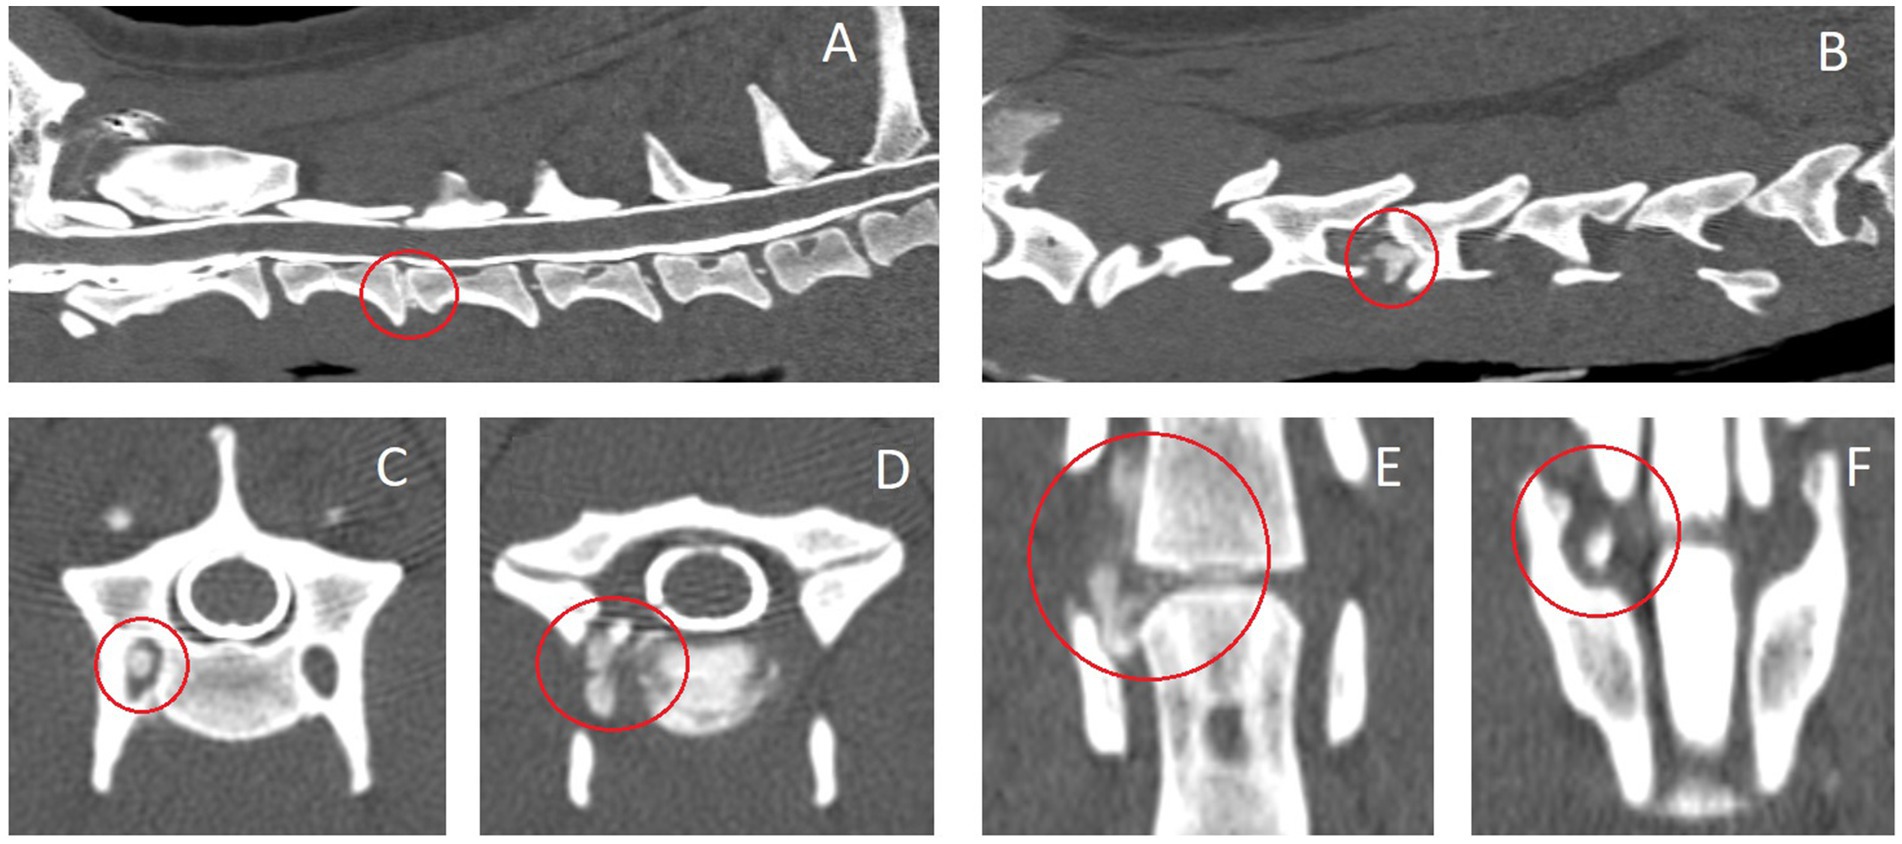

En la Tabla 2 se incluye un resumen de las modalidades de diagnóstico por imagen empleadas y los hallazgos. Las IVDE cervicales laterales lejanas se diagnosticaron con resonancia magnética de alto campo en 6/10 (60%) perros (ejemplos en las figuras 2, 3), mielograma por TC en 2/10 (20%) perros (ejemplo en la figura 4) y TC y resonancia magnética de campo bajo en 2/10 (20%) perros. Un perro (1/10, 10%) tenía un IVDE lateral lejano (C2-3, izquierda) y un IVDE lateral lejano/foraminal (C3-4, izquierda). Por lo tanto, informamos las características de 11 IVDE. Se diagnosticó IVDE lateral lejano en todos los perros (10/10, 100%); 6/11 (55%) fueron IVDE foraminales/laterales lejanos. La lateralización fue hacia la izquierda en 7/11 (64%) y hacia la derecha en 4/11 (36%) IVDEs. Todas las extrusiones laterales lejanas y la combinación de extrusiones laterales/foraminales se encontraban al nivel de un espacio IVD reducido en comparación con los espacios IVD adyacentes, y IVD parcialmente mineralizado (hiperatenuante en la TC, marcadamente hipointenso en todas las secuencias en la RM). Los espacios IVD afectados fueron: C3-4 (6/11, 55%), C5-6 (3/11, 27%) y C2-3 (2/11, 18%). A partir de las imágenes de TC, todas las extrusiones foraminales y laterales lejanas eran homogéneas y mineralizadas (hiperatenuantes a la médula espinal, HU > 500). A partir de las imágenes de resonancia magnética, las lesiones extradurales eran ligeramente heterogéneas, pero predominante y marcadamente hipointensas en todas las secuencias, compatibles con mineralización. Al comparar entre las secuencias de resonancia magnética, el material extradural fue T2W y T1W isointenso al hueso cortical, y esto resultó en una disminución de la visibilidad en las imágenes T2W en comparación con las imágenes T1W y T2*W (Figuras 1, 2). En todos los casos, la lesión extradural causó efecto de masa y la consiguiente falta de visualización de la arteria vertebral y el nervio espinal a lo largo de la longitud donde se localizó el material extradural. A partir de las imágenes de resonancia magnética, las secuencias de supresión de grasa (la mayoría de ellas STIR dorsal) revelaron una hiperintensidad leve y mal definida de los músculos epaxiales y los tejidos perineurales alrededor del material extruido. La lateralización de los signos clínicos coincidió con la lateralización de la IVDE lateral lejana (en las imágenes) en todos los casos en los que se observó lateralización.

Figura 4. Imágenes tomográficas computarizadas (con medio de contraste intratecal – mielograma) del caso #2 con una extrusión de disco intervertebral C3-4 lateral derecho y foraminal. A: reconstrucción del plano medio sagital, B: reconstrucción parasagital derecha a nivel del pedículo derecho de C4, C: plano transversal a nivel de la cara craneal de C4, D: plano transversal a nivel del disco intervertebral C3-4, E: reconstrucción del plano dorsal a nivel del foramen transverso de la vértebra C4, F: Reconstrucción del plano dorsal a nivel del foramen intervertebral. El disco intervertebral afectado y el material del disco extruido hiperatenuante están rodeados con un círculo rojo.

En nuestro estudio, 10 perros tenían 11 IVDEs: 6/11 eran IVDE combinados far-lateral/foraminal y 5/11 eran IVDE pura far-lateral (es decir, el material extruido se localizaba distal al foramen, lateral al IVD). Las IVD laterales lejanas en perros se han descrito con mayor frecuencia en la zona toracolumbar, afectando principalmente a las IVD lumbares caudales (L5-6 y L6-7) (7). La falta de publicaciones sobre las IVED cervicales en extremo sugiere que rara vez se diagnostica. El conocimiento de este tipo de IVDE sigue siendo de vital importancia para los clínicos, especialmente para aquellos que realizan e interpretan estudios de diagnóstico por imagen. Todas las extrusiones de disco foraminal/far-distal incluidas en este estudio estaban mineralizadas y estaban al nivel de un espacio de disco intervertebral estrecho con un disco intervertebral parcialmente mineralizado. Dado que las lesiones mineralizadas y las estructuras óseas se evalúan bien a partir de las imágenes de TC, estas lesiones eran obvias y se diagnosticaban fácilmente mediante TC. La mineralización puede ser más difícil de describir a partir de estudios de resonancia magnética y, por lo tanto, cuando se sospecha una extrusión de disco foraminal/distal lejano, es importante incluir varias secuencias y varios planos.

En cuanto a la TC, la TC parasagital reconstruida muestra la presencia de material hiperatenuante lateralmente si el material del disco está calcificado (degenerado) (Figura 4). El uso de medio de contraste intratecal no iónico (mielograma por TC o mielotomografía computarizada) en este tipo particular de enfermedad IVD podría no agregar ningún valor a menos que haya una compresión concomitante de la médula espinal por parte del material del disco extruido o compresiones adicionales de la médula espinal que afecten a otros espacios de IVD. Sin embargo, cuando se utiliza un medio de contraste intravenoso no iónico, puede revelarse una pérdida de continuidad de la señal de la arteria vertebral de forma más conspicua que en los estudios de resonancia magnética. Al igual que en la resonancia magnética, la reconstrucción del plano dorsal y las imágenes del plano transversal a nivel del IVD pueden proporcionar una mayor confirmación y evaluación del material del disco extruido lateralizado. La distribución del material de disco extruido mineralizado puede visualizarse de manera aún más visible en las imágenes de TC que en las imágenes de RMN. Esto se ejemplifica en la Figura 4C, donde el material del disco extruido y calcificado se puede visualizar en la cara craneal del foramen transverso, comprimiendo las estructuras del mismo (por ejemplo, la arteria vertebral).